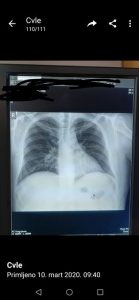

– Reč je o Influenci A, sezonskom gripu. Imao je srčanu slabost i slabost pluća. On je 10 dana osećao slabost organizma, mi smo u subotu insistirali da on bude hospitalizovan, na šta je pristao posle podne. Prebačen je na koronarnu jedinicu i nažalost preminuo je – rekao je za medije direktor Sazdanović. Hirurg Vladimir Đorđević iz Kragujevca objavio je fotografiju pluća preminulog pacijenta sa razlikom od jednog dana, kako bi ukazao na opasnosti virusa gripa i kako bi apelovao na građane da se ne leče „rakijom i belim lukom“. Iako još uvek nisu stigli rezultati obdukcije koji će potvrditi da je u pitanju običan virus, pluća pacijenta su ista kao kod osoba koje su preminule od korona virusa – tvrdi ovaj doktor.

– Nema šta da se objašnjava, ne mogu ovde da držim kurs medicine. Razlika je toliko upadljiva, zato sam okačio kao razglednicu posebno za one što se leče rakijom i belim lukom – napisao je dr Đorđević na Tviteru priznavši da je možda napravio propust što je tako nešto okačio, ali evidentno iz pametnih i opravdanih razloga. Kako i sam kaže slika preminulih od gripa i od korona virusa je ista. – Radi se o preminulom mladiću (25) u nedelju u Kragujevcu, navodno običan grip. Svrha tvita je da ukaže zašto su na respiratoru. I slepac vidi razliku, ne trebaš biti lekar. Isti bolesnik, razlika jedan dan – zaključio je. Prof. dr Predrag Sazdanović je dodao da je „pacijent 1995. godište i da je u nekom periodu kao vozač išao po auto-delove u Sloveniju“. Sazdanović naglašava da je Institut Torlak potvrdio da je pacijent imao sezonski grip, Influencu A, kao i da će uslediti obdukcija preminulog.